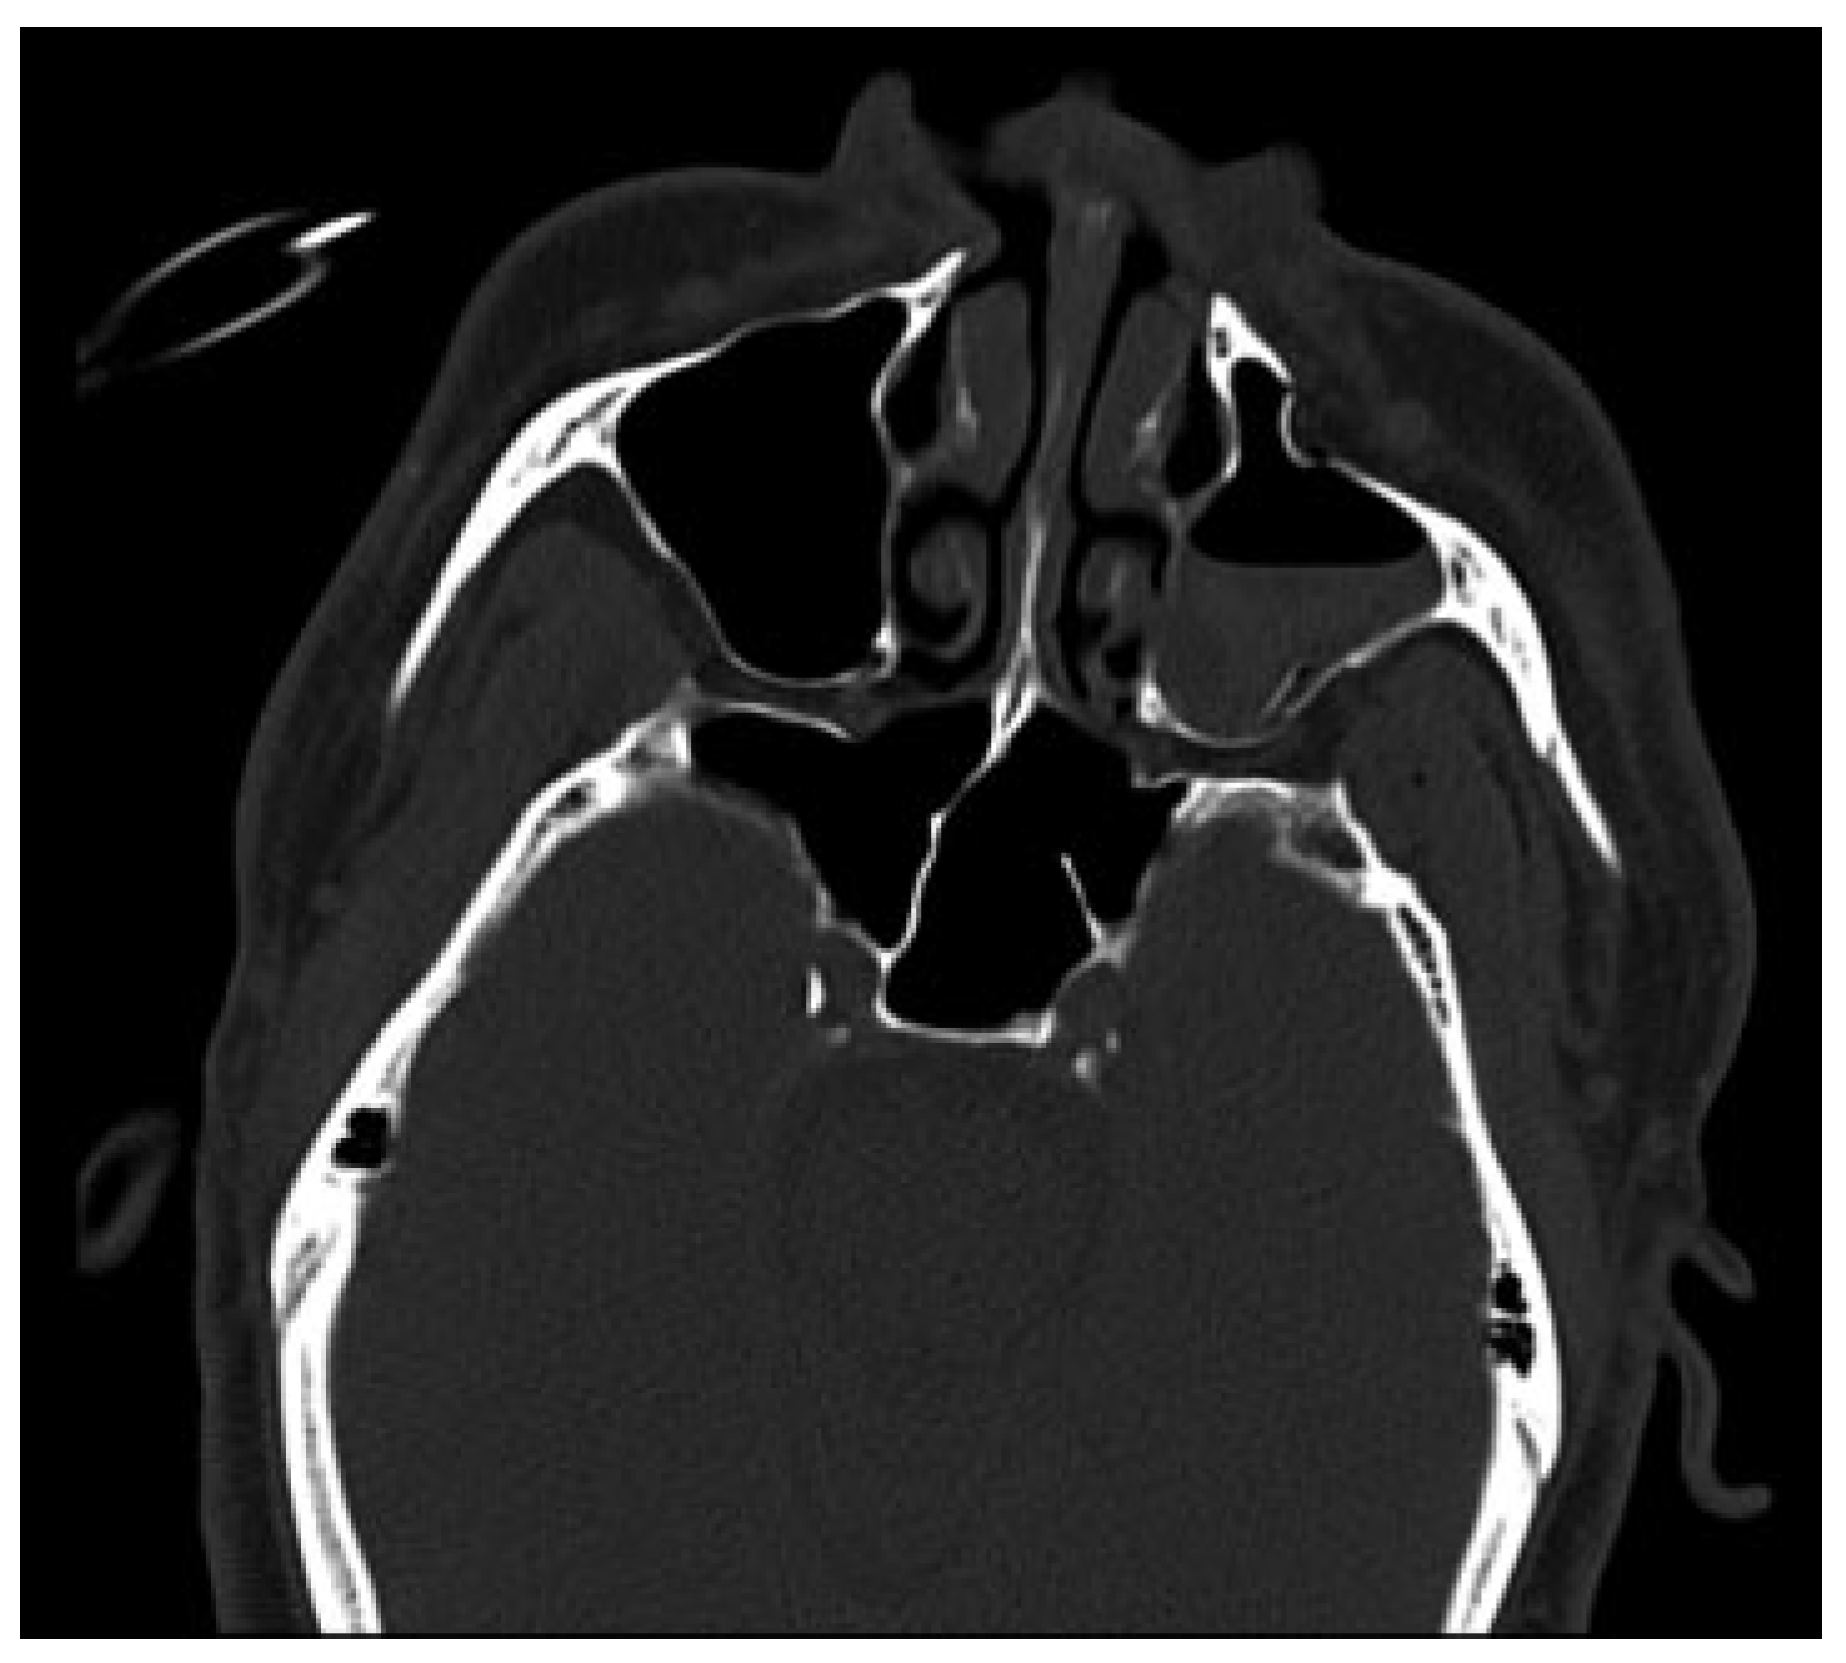

Subsequently, the diagnosis was made of a left zygomaticomaxillary complex (ZMC) fracture with associated SOFS caused by compression of the fissure by bony segments. After discussion of treatment options, an open reduction with internal fixation of the left ZMC fracture was performed under general anesthesia using lateral brow and a maxillary vestibular incision with hopes of minimizing the bony impingement of the superior orbital fissure. The patient was given a perioperative dexamethasone taper beginning with an immediate preoperative dose of 10 mg. A postoperative maxillofacial CT was obtained to evaluate the reduction and reassess the left superior orbital fissure (Figure 5 and Figure 6). The patient was followed weekly by the Oral and Maxillofacial Surgery service as an outpatient. The patient’s SOFS resolved completely (Figure 7).

Figure 6. Comparison of the pre- and postoperative maxillofacial computed tomographic scans. Both images are axial cuts, bony windows, at the approximate level of the superior orbital fissure. Note the second image demonstrating widening of the superior orbital fissure, verified by radiological report, with decreased bony compression and excellent reduction of the fracture segment.